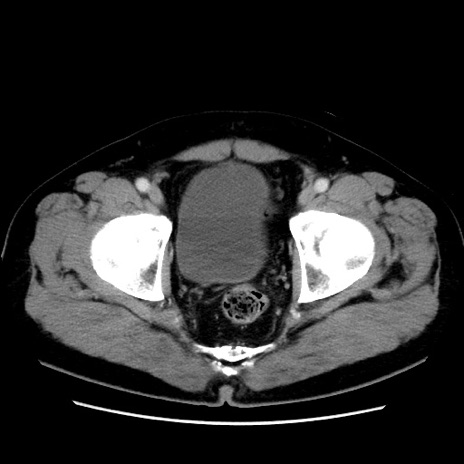

冠状断像